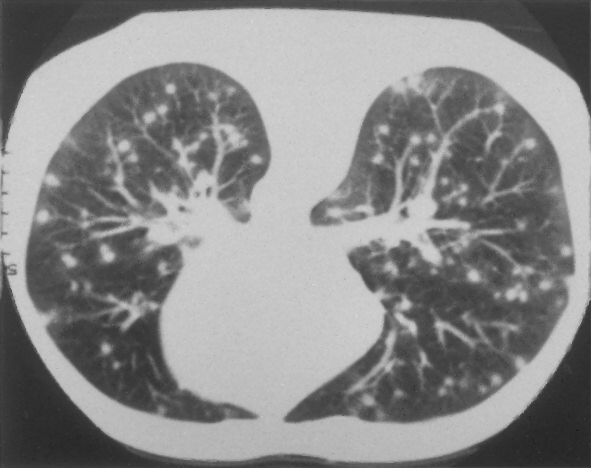

In the second part of this example, we consider the restoration of the same three medical test images corrupted by the same blur of parameters

band=5 , sigma=1 and by a different impulsive noise, namely AWLN of level yielding BSNR=10. In Table 2 we report the ISNR values achieved by the compared methods and in Fig. 8 we show the original images, the corrupted images and the restored images by our model.

The results in Table 2 confirm that, also in case of images corrupted by AWLN, the proposed TV-L1 model outperforms

its competitors in terms of ISNR. Moreover, the restored images depicted in the last column of Fig. 8 provide further evidence of the good quality restorations achievable by our proposal.

![]() |

| (a) original | (b) original | (c) original |

| (d) corrupted (BSNR=10) | (e) corrupted (BSNR=10) | (f) corrupted (BSNR=10) |

| (g) TV-L1 | (h) TV-L1 | (i) TV-L1 |

| TV-L1 | TVp-L1 | TV-L1 | TV-L1 | |

|---|---|---|---|---|

| lungs | 6.20 | 6.80 | 7.30 | 7.85 |

| ecography | 5.93 | 6.40 | 7.88 | 8.32 |

| aneurism | 9.10 | 9.44 | 10.13 | 10.70 |